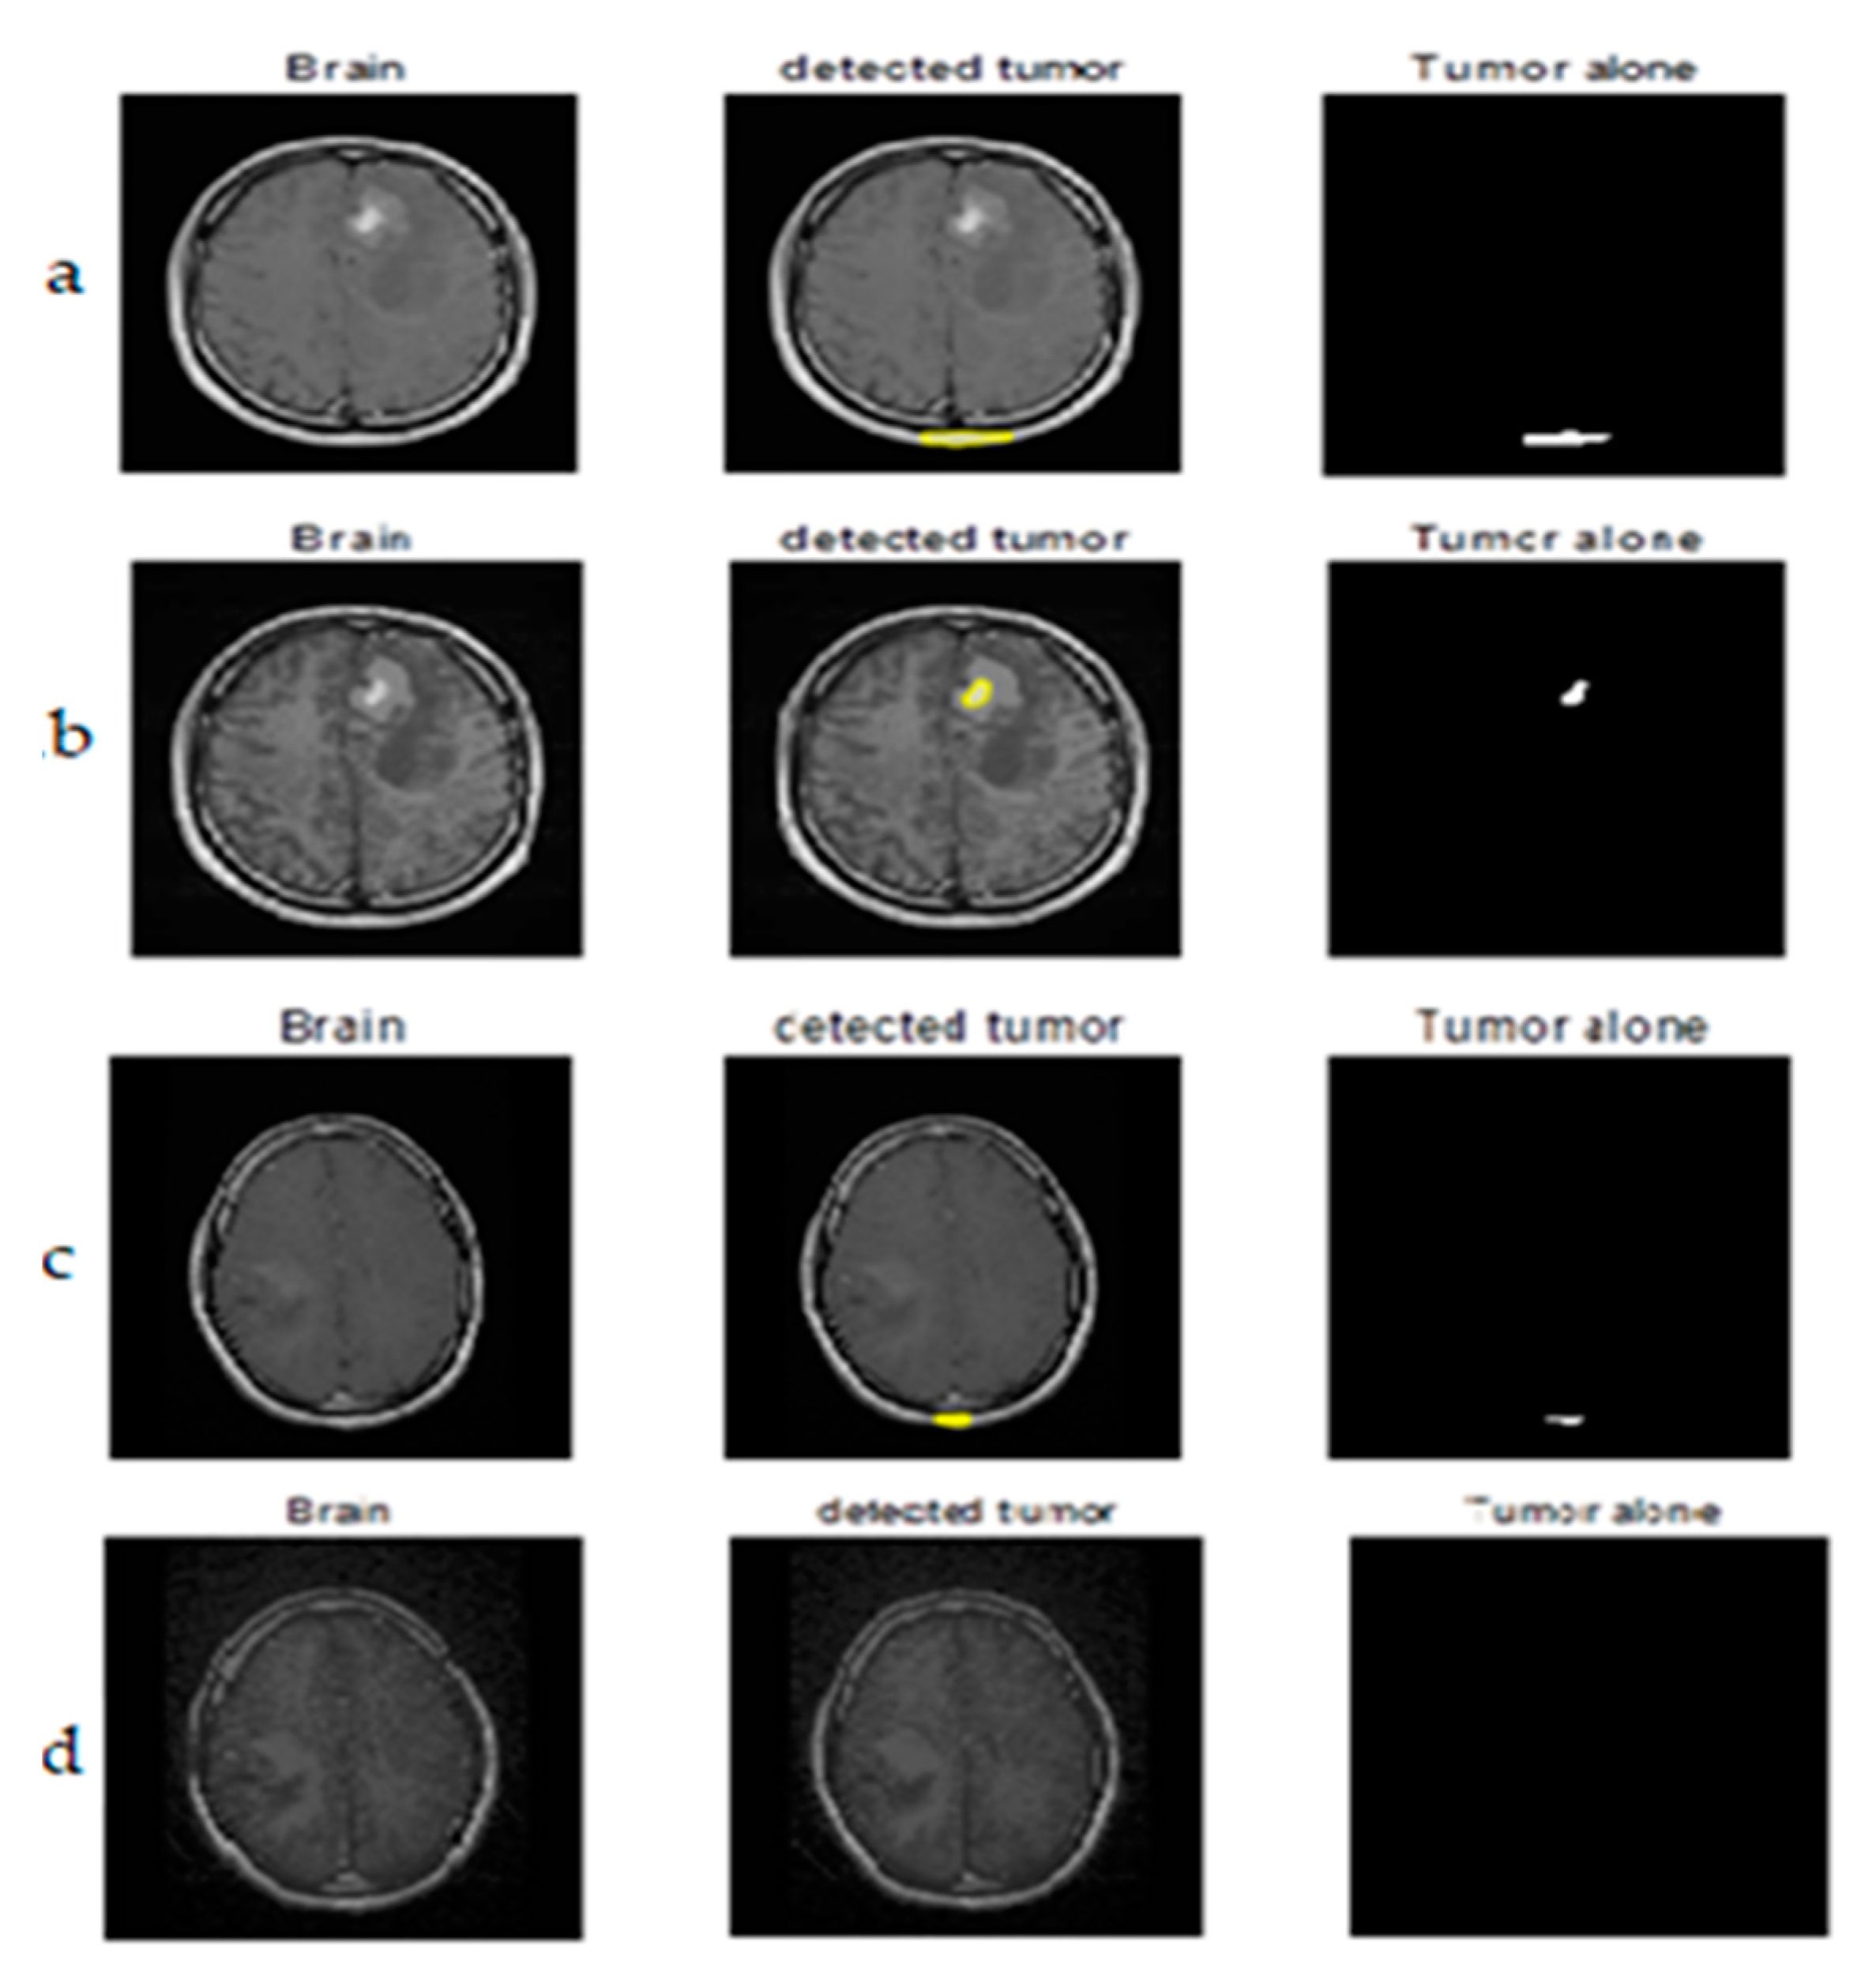

Segmentation results of the proposed method are shown in Figure 11 and Figure 12. The obtained numerical values are tabulated in Table 5 and Table 6 respectively, including the performance measures of dice similarity and Jaccard index. The proposed method provides efficient and robust results when compared to the FCM technique by a mean of a 98.86% dice index and 96.9% Jaccard index. This helps the physician to check whether the presence of any abnormalities is available in the MRIs corresponding to different parts of the brain. We conclude that the proposed remodified FCM technique ARKFCM method is more robust to noise and shading effects; the major advantage of using this technique is locating the tumor and affected regions.

Figure 11.

Tumor detection from original MRI brain images. (a) the first image in the is the original image, the second image is the segmentation image of the first image after preprocessing, and the third image represents detection of tumor alone. (b–d) rows consists of original brain images, segmented image with detected tumor, segmented tumor alone with proposed method respectively.

Figure 12.

In the figures, the first image in the is the original image, the second image is the segmentation result of the first one, and the third image represents the extraction of the tumor succeeding segmentation. Similarly, in Figure 12, row 2 (b), the first figure is the preprocessed result of the original image, and the second and third images are same as above. From the third part, it is visualized with ease that the result of the tumor extraction does have more precision in the case of part ‘(b)’ compared to part ‘(a)’.